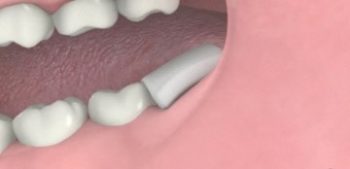

5. ทันตแพทย์เอาฟันคุดออกมา